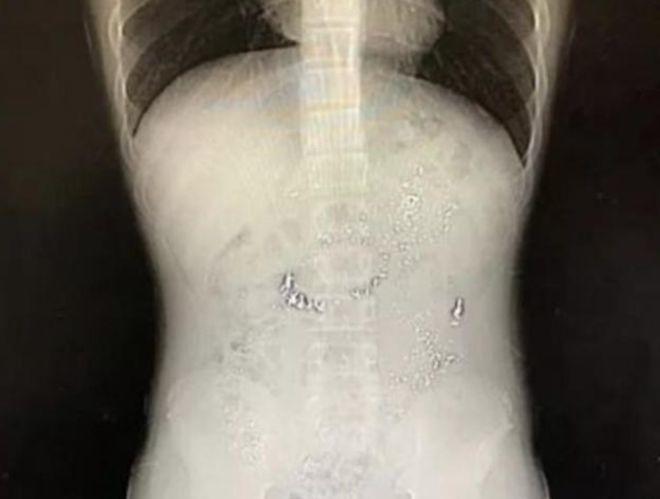

Hình ảnh chụp X-quang cho thấy bé trai đã nuốt một lượng nhỏ thủy ngân vào trong bụng. Tuy nhiên phía bác sĩ cho biết niêm mạc dạ dày không bị tổn thương nên lượng nhỏ thủy ngân này sẽ bị đào thải ra ngoài. Bố mẹ nên cho con ăn nhiều chất xơ thô như cần tây, tỏi tây. Bên cạnh đó, phía bác sĩ dành lời khen ngợi cho cách sơ cứu của người bố là hoàn toàn đúng đắn và rất chuyên nghiệp.